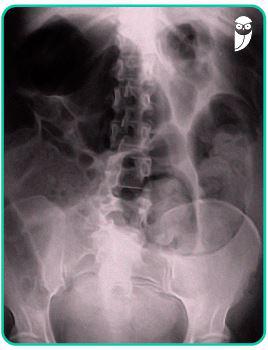

Paciente masculino, 67 anos, admitido na emergência queixando-se de dor abdominal em cólica, iniciada há 4 dias, com piora progressiva desde então. Refere que há 5 horas vem apresentando vômitos “esverdeados” e que não evacua desde o início do quadro, e hoje não eliminou flatos. Relata ainda que apresentou dois episódios de hematoquezia nos últimos 04 meses. Nega comorbidades conhecidas. Ao exame físico: REG, descorado 2+/4+, desidratado 2+/4+, anictérico, afebril. FC 102 bpm. PA 110 x 80 mmHg. FR 16 irpm. Abdome globoso, distendido, doloroso à palpação, timpânico. Sem sinais de irritação peritoneal. Toque retal: massa palpável na luz retal, endurecida, a cerca de 06 cm da borda anal, estenosante. Exames complementares: Hb 8,9 / Ht 26,7 / Leucócitos 12.500 cel/mm3, sem desvio / Cr 1,2 / Ur 40 / Na 143 / K 3,9. Realizada radiografia de abdome (imagem a seguir) e tomografia computadorizada de abdome e pelve com contraste, que identificou tumor no reto, de aproximadamente 5 cm de extensão, estenosante, provável T3. Sem sinais de doença hepática ou peritoneal.